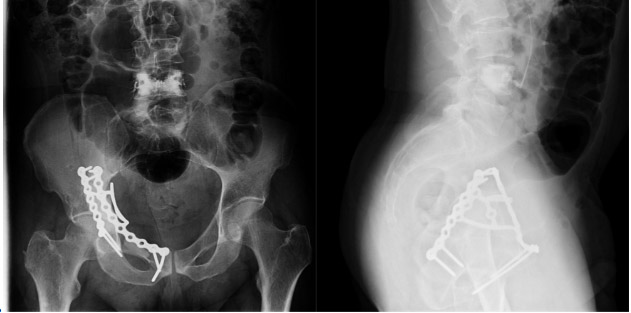

Postoperative: The X-ray shows that after the metastatic focus was removed, the resulting cavity was filled with bone cement and reinforced with two titanium plates (Simultaneous closed cementation/vertebroplasty procedure was performed on the L5 vertebra).